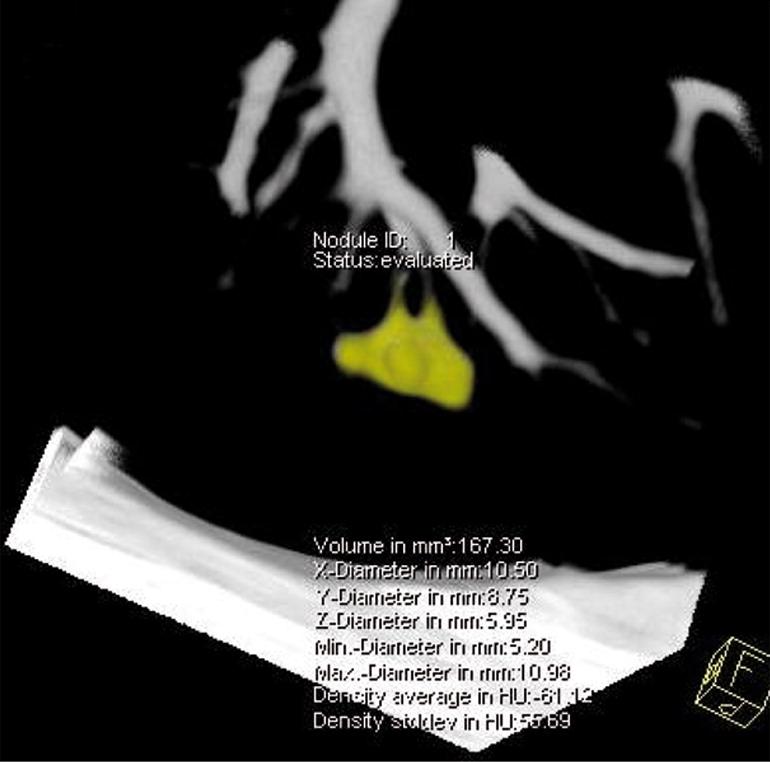

In NELSON, 10.7% of participants had solid, intraparenchymal nodule with volume 50-500 mm^3

About 10% of solid intraparenchymal nodules of intermediate size resolve during followup